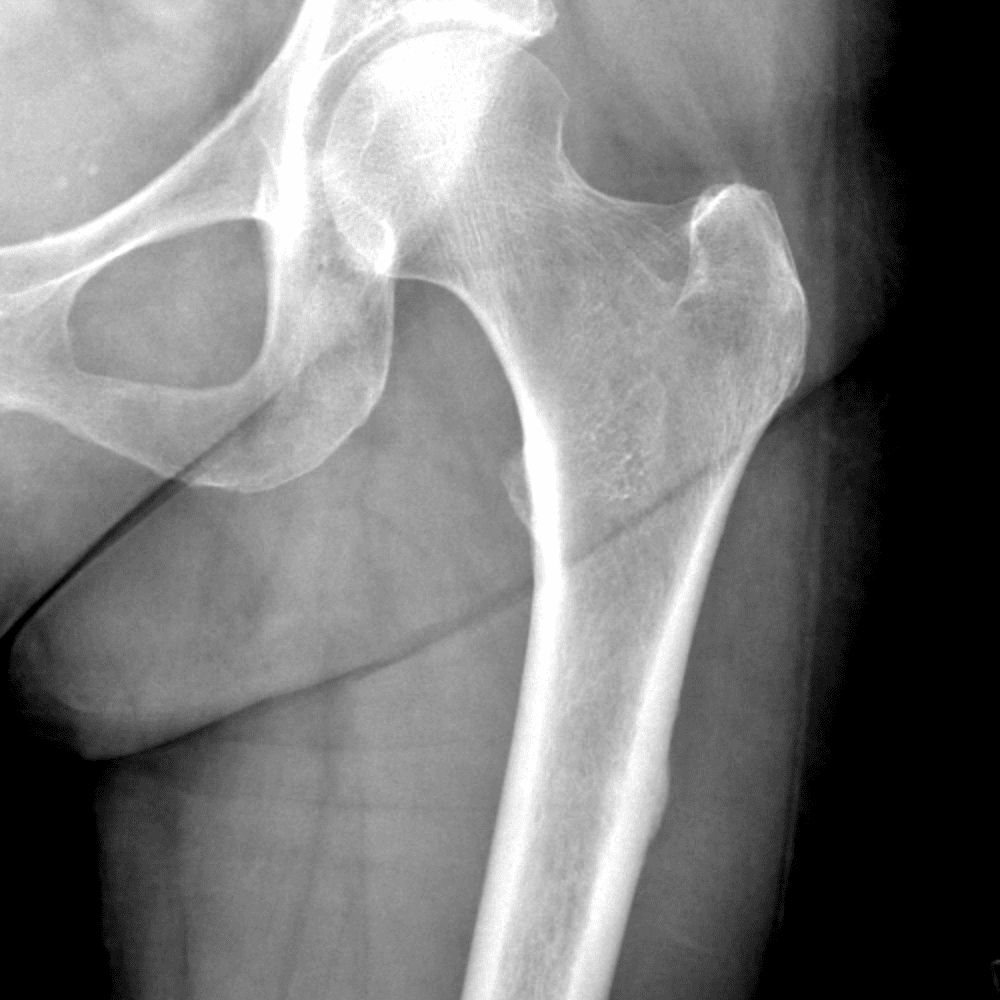

通过包含微妙或困难的病例和一些正常病例来模拟值班。